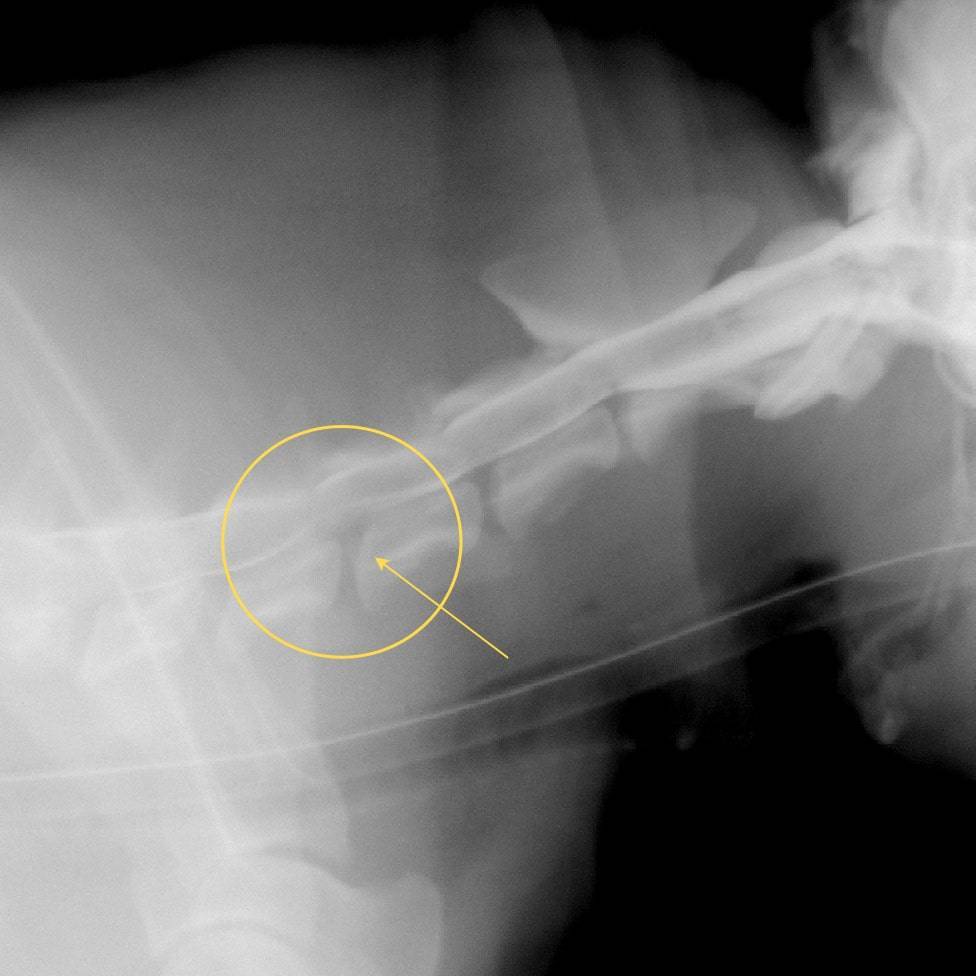

При исследовании крови отмечено повышение уровня тропонина. Ларри выполнена субэндокардиальная биопсия миокарда (СЭБМ – Олейников Д.А.) под контролем электронно-оптического преобразователя (ЭОП). При проведении процедуры отмечено образование перед сердцем в проекции загрудинного лимфатического узла.

Рисунки 2 и 3. Процедура выполнения СЭБМ (вид через ЭОП). На рисунке 3 прохождение манипулятора затруднено крупным образованием в проекции загрудинного лимфоузла.